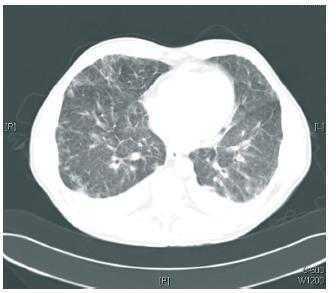

Los hallazgos de laboratorio mostraban 3.980 leucocitos/μl (eosinófilos 29,3%), hemoglobina 12,1 g/dl, plaquetas 276.000, creatinina 1,79 mg/dl, sodio plasmático 138 mEq/l, potasio plasmático 3,9 mE/l, y niveles plasmáticos de everolimus de 14 ng/ml. En la radiografía de tórax se observó un patrón intersticial bilateral, y en la TAC torácica, infiltrados y nódulos pulmonares con engrosamiento del intersticio bilateral (figura 1 y figura 2). La antigenemia y cultivo de citomegalovirus (CMV) fueron negativos, así como el antígeno de neumococo y Legionella. Se realizó broncoscopia con signos de broncopatía crónica, con resultados de BAL y BAS negativos. Se inició tratamiento empírico de amplio espectro antibiótico y antiviral, sin mejoria clínica y con empeoramiento radiológico, por lo que, con sospecha de neumonitis por everolimus, se decidió la retirada de este fármaco y la introducción de tacrolimus. El día posterior a la retirada de everolimus el paciente presenta mejorías clínica y radiológica progresivas con resolución del cuadro.

Figura 2. TAC torácica